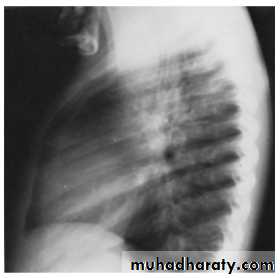

In infantile type ECG and CXR show right ventricular hypertrophy with cardiomegaly and pulmonary edema while in older children they show left ventricular hypertrophy and a mildly enlarged heartIn older children(>8 years) the chest x-ray film may show notching

of the ribs due to the development of collaterals.